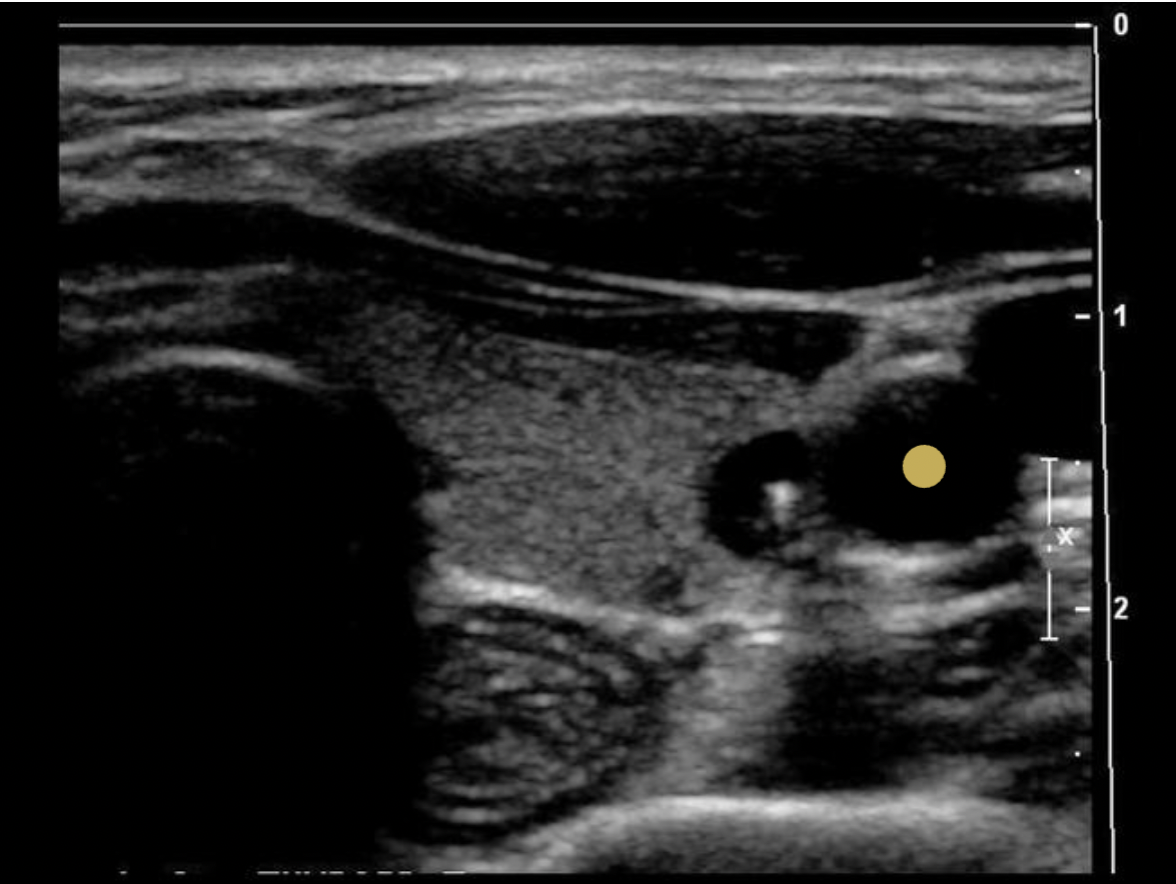

Which of the following correctly describes the findings on the image?

C. There is an appendix teste present

The appendix teste is a small ovoid structure usually located between the superior pole of the testicle and epididymal head. It is normally the same echogenicity of the epididymis.